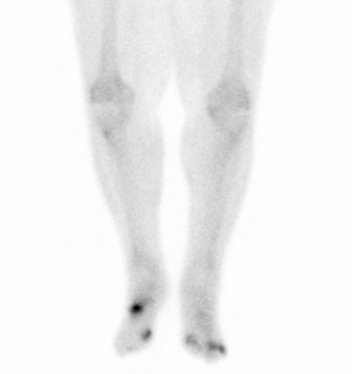

Metastatic Tumors to the Bone

Primary cancers are less frequent than metastatic tumors to the bone.

Metastatic tumors to the bone typically show osteolytic, punched-out lesions on X-ray.

Notably, metastatic prostate cancer to the bone produces osteoblastic lesions.